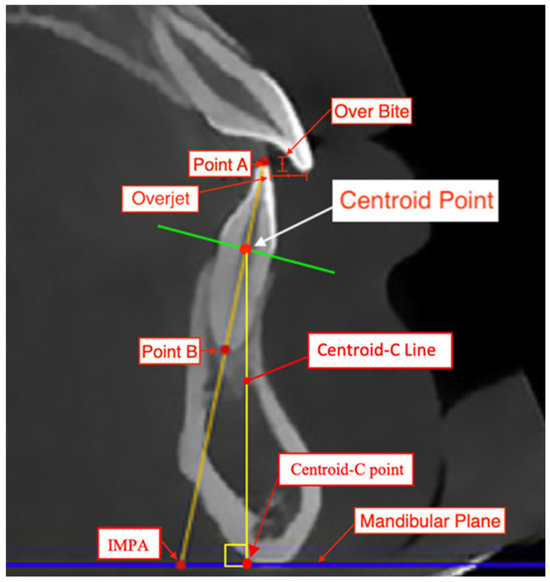

All measurements were conducted by one examiner (CB) who was pre-calibrated and trained in cephalometric assessment. The same examiner (CB) remeasured records from 10 randomly selected patients to assess intra-observer reliability. A second calibrated examiner (AG) measured records from 10 randomly selected patients to assess inter-observer reliability. The methodology for assessment will be similar to that in the study by Al-Balaa et al. [7] in determining the total intrusive movement of mandibular central incisors. First, the landmarks of a centroid point were established at the intersection of a horizontal line constructed from the cementoenamel junction (CEJ) of the facial and lingual surfaces of the lower central incisor and the vertical axis of the lower central incisor on a lateral cephalogram (Figure 1). The IMPA, L1 to APo, and L1 to NB were established using Dolphin software version 11.95 and the Steiner [12], Tweed [13], and Ricketts [14] cephalometric analyses (Figure 2). These measurements were made on pre-treatment (T1) and on post-treatment (T2) lateral cephalograms. A tooth’s total intrusion was determined by the decrease in distance from the centroid point to the mandibular plane (Centroid-C Line) in T1 to T2. IMPA, L1 to APo, and L1 to NB were also recorded for T1 and T2. The total intrusion of each tooth was then contrasted with the total intrusive movement predicted in the ClinCheck software [15,16,17,18]. The change in inclination of IMPA, L1 to APo, and L1 to NB from T1 to T2 were also contrasted with the predicted degree of change in the ClinCheck software.

Figure 1. Lower incisor intrusion measurement landmarks. Point A (incisal tip): most coronal point of lower mandibular anterior tooth from sagittal view at buccolingual and mesiodistal midpoint. Point B (root apex): most apical point of lower mandibular anterior tooth from sagittal view at buccolingual and mesiodistal midpoint. Centroid-C Point: intersecting perpendicular point of Centroid-C line with mandibular plane. Centroid point: central point of lower central incisor identified from midpoint formed from buccal and lingual CEJ. AB line: line segment created from A point to B point and total estimated length of tooth. Centroid-C line: line segment from tooth centroid to mandibular plane forming right angle at mandibular plane and estimated spatial vertical position. Overbite: overlapping of mandibular central incisor teeth by maxillary central incisor teeth. Overjet: extent of anterior–posterior of maxillary central incisor to mandibular central incisors.